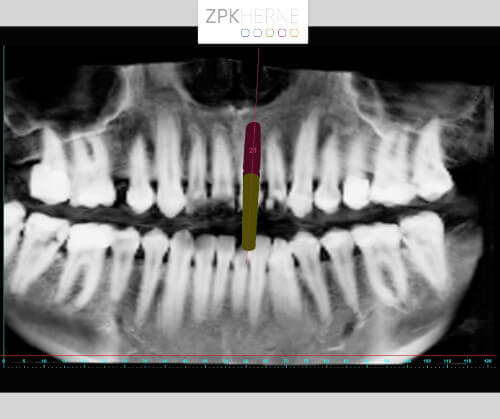

Radiologische Aufnahme mit entzündeter Wurzelspitze

Implantatplanung mittels Simplant